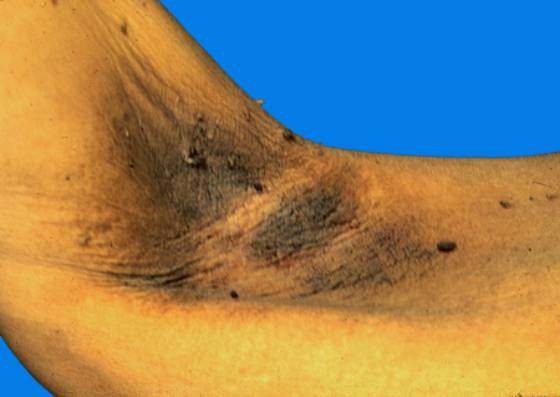

黑棘皮病(acanthosis nigricans)

黑棘皮病(acanthosis nigricans)特征为皮肤色素沉着、粗糙,伴疣状、乳头瘤状增殖,发病可能与遗传、内分泌、药物、及肿瘤等因素有关。

1.皮损好发于颈部、腋部、外生殖器、腹股沟、肛周、脐窝、乳晕及面部等处。

2.主要损害为患处皮肤灰褐色或黑色,增厚、粗糙呈疣状和小乳头状,触之似天鹅绒状。临床因病因不同病情各异。

3.恶性型 中老年发病,皮损严重,色深,广泛,有掌跖角化,消瘦,常伴内脏恶性肿瘤,见图13、14。